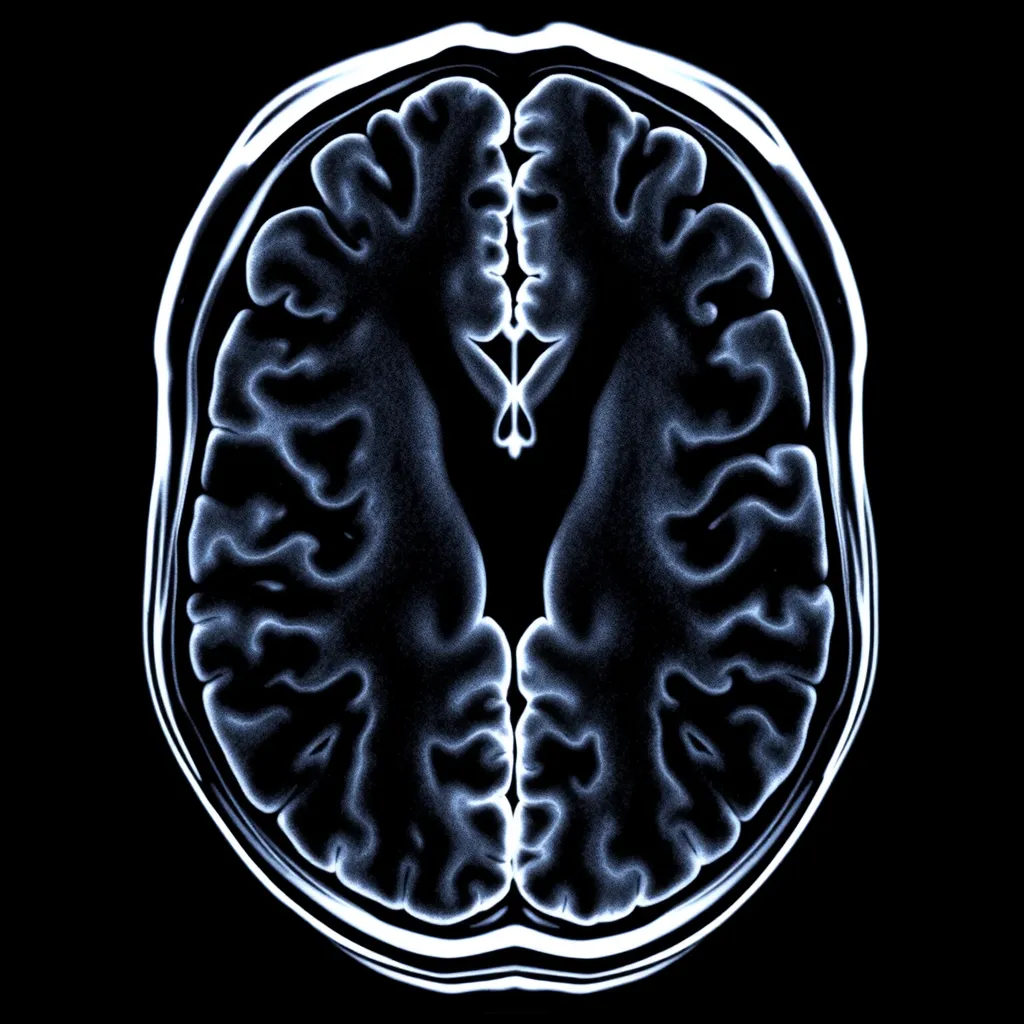

Magnetic Resonance Imaging (MRI) is a revolutionary medical imaging technique that has become indispensable in modern diagnostics, It provides detailed images of the body’s internal structures offering unparalleled insights into various medical conditions.

Explanation of How MRI Technology Works

MRI uses powerful magnetic fields, radio waves, and a computer to produce detailed images of the body’s internal structures. The process involves placing the patient inside a large magnet, which aligns the hydrogen atoms in the body. Radio waves are then sent through the body, causing the hydrogen atoms to emit signals.

These signals are detected by the MRI machine and converted into images by a computer.

Description of fMRI and Its Role in Mapping Brain Activity

Functional MRI (fMRI) is a specialized type of MRI that measures brain activity by detecting changes in blood flow. When a specific area of the brain is active, it receives more blood flow, which can be detected by fMRI.

This technique is crucial for understanding brain function and mapping different areas of the brain.